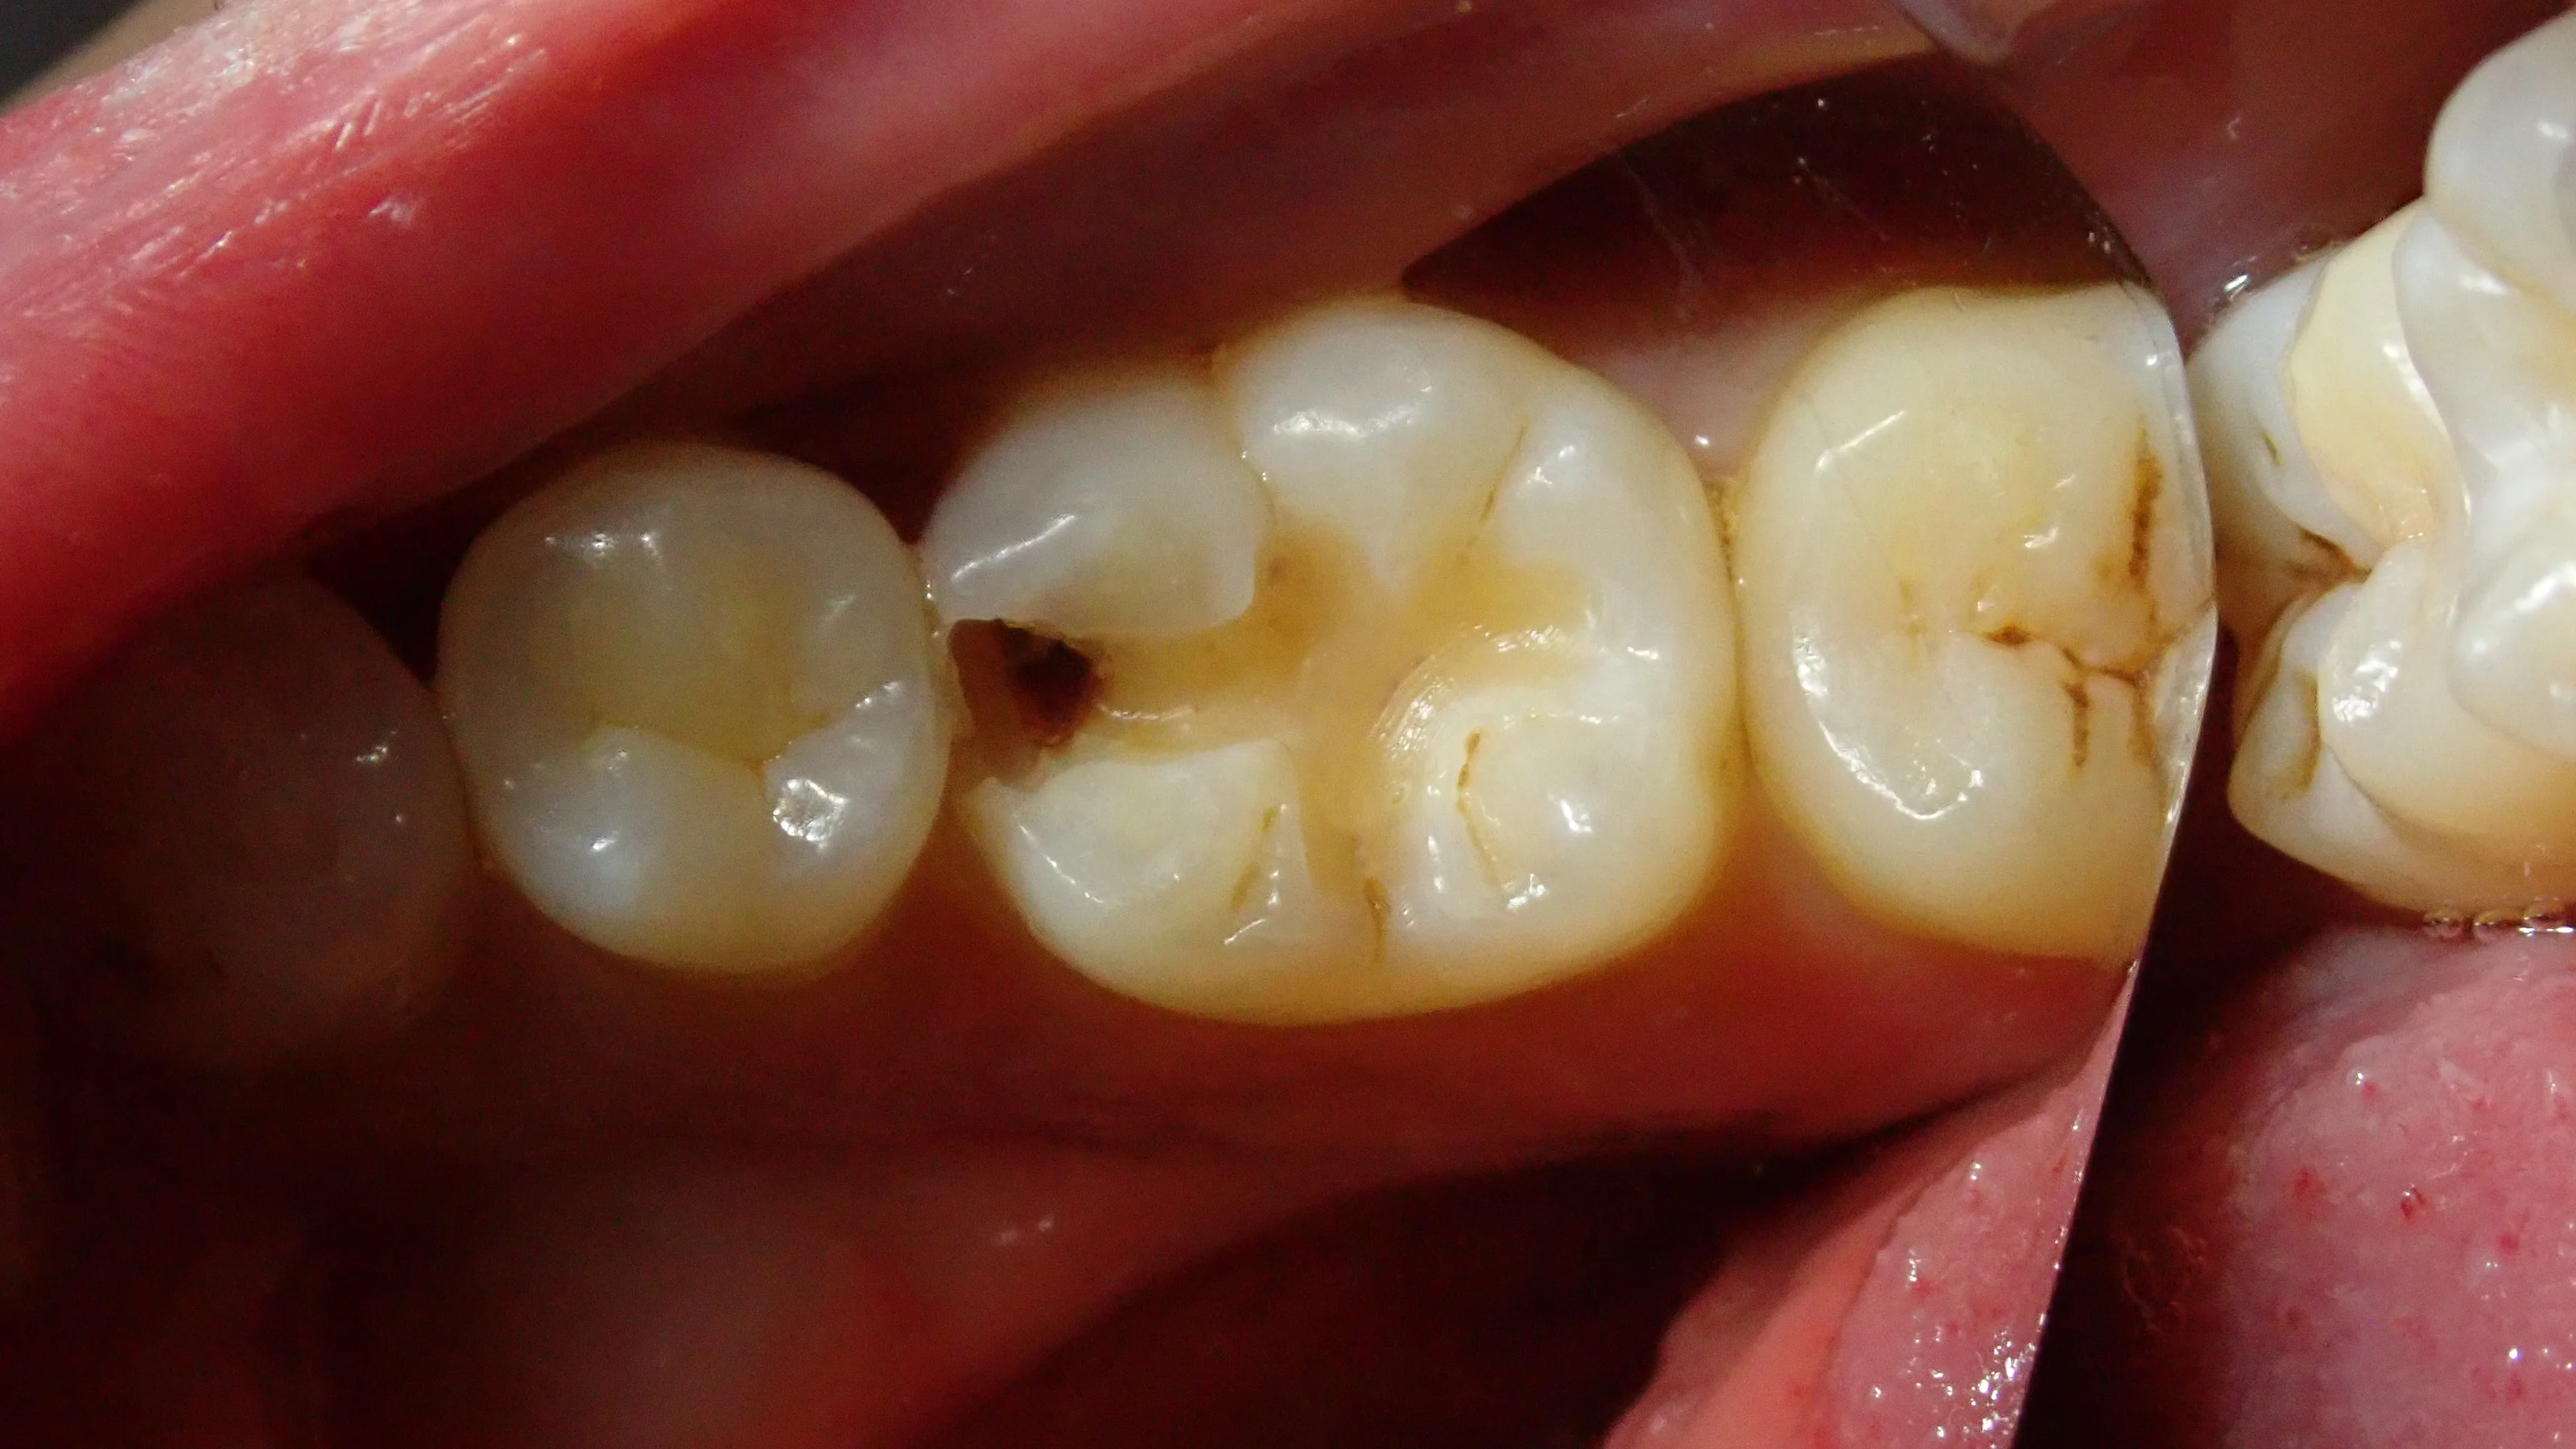

まずは術前の写真です。

どうやら保険適用内のCR(コンポジットレジン)で治療を受けられたようですが、割れてしまい、そこから中に虫歯が侵入してしまったようですね。